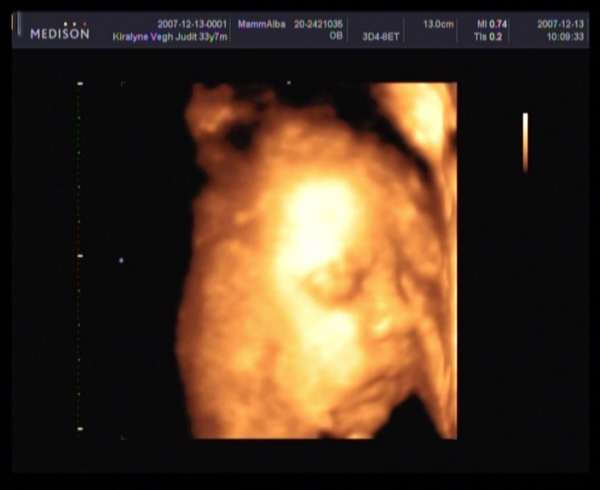

Judy,

gyere a képekkel!!!! Nagyon kíváncsi vagyok Barbikára!!!!!